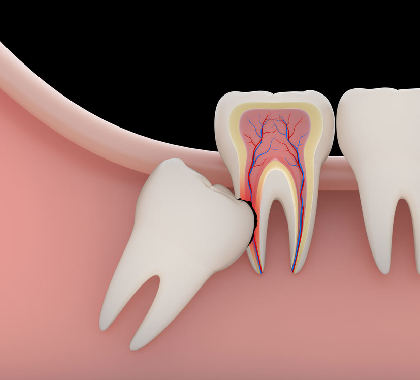

Tooth Extractions

A tooth extraction is a procedure to remove a tooth from the gum socket.

Root Canal Treatment

A dental procedure involving the removal of the soft center of the tooth, the pulp.